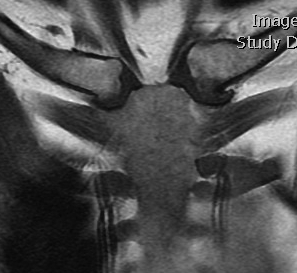

Left posterior SCJ dislocation with pre- and post angiogram

Left posterior SCJ dislocation with pre- and post angiogram